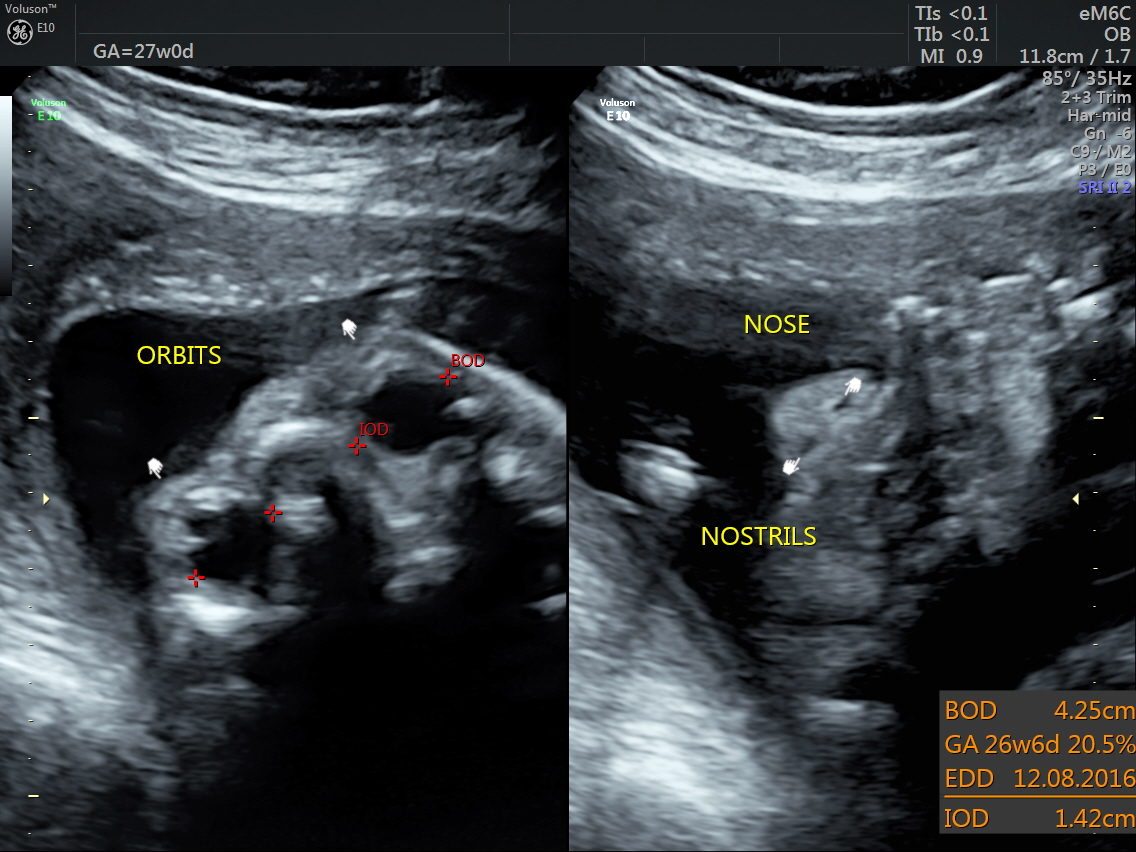

RT AORTIC ARCH_6 Published June 17, 2016 at 1136 × 852 in Rt aortic arch and aberrant left subclavian artery ← Previous Next →